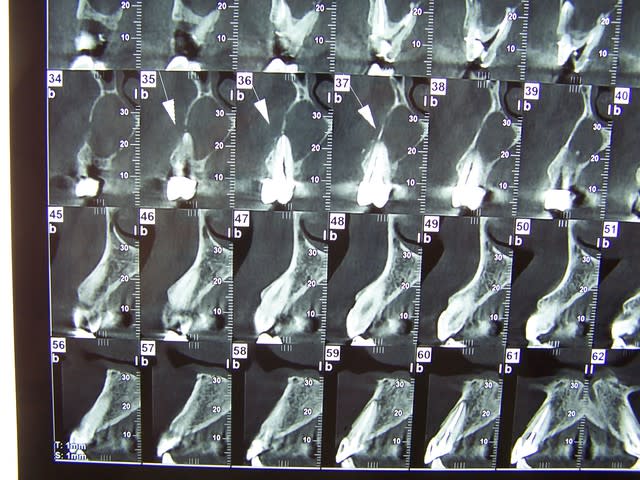

100 0228 vvtb6q - Eugenol

100 0237 a8szpj - Eugenol

100 0242 ykl54n - Eugenol

100 0239 e8iqyw - Eugenol

100 0244 jqiuru - Eugenol

100 0246 zajevt - Eugenol

100 0241 xcf8hl - Eugenol

100 0240 h5qp8d - Eugenol

100 0243 njsenm - Eugenol

100 0247 n13vtf - Eugenol